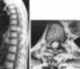

Primary spinal tumor

Spinal tumors are neoplasms located in either the vertebral column or the spinal cord. There are three main types of spinal tumors classified based on their location: extradural and intradural (intradural-intramedullary and intradural-extramedullary). [Source: Wikipedia ]